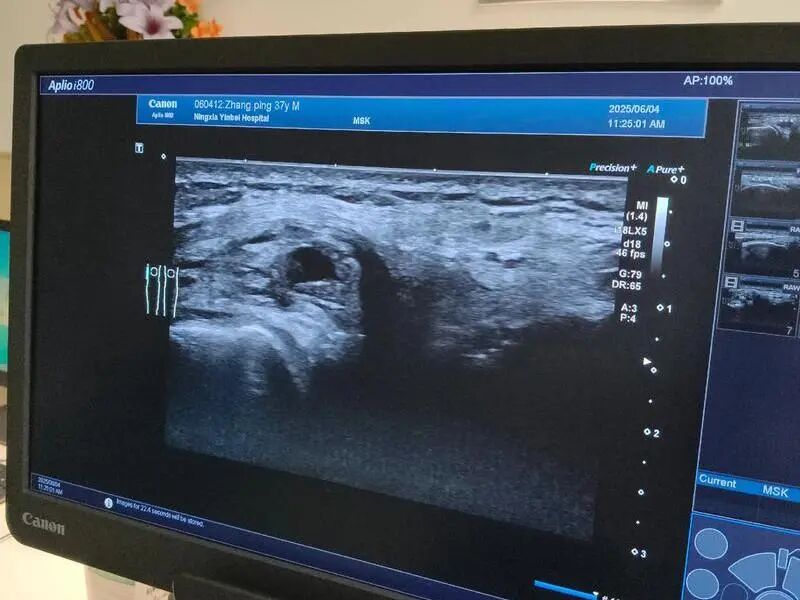

尿酸结晶沉积是痛风确诊的关键依据,通过肌骨超声,能清晰看到结晶的数量和分布,直观反映病情轻重。

若检查发现结晶较多,需在医生指导下加强调理或治疗,避免结晶进一步形成痛风石、损伤肾脏。